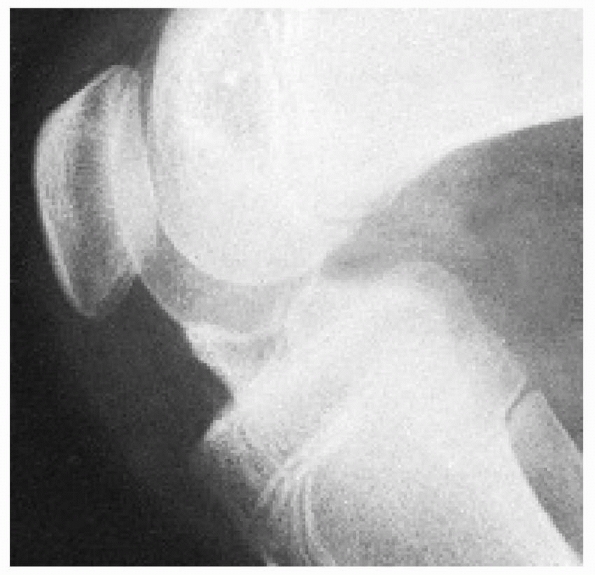

best on the lateral and tunnel views. The lateral radiograph is most

useful in fracture classification. Radiographs should be carefully

scrutinized as the avulsed fragment may be mostly nonossified cartilage

with only a small, thin ossified portion visible on the lateral view.

ascertain from the radiographs includes the classification type, amount

of displacement, size of the fracture fragment, comminution of the

fracture fragment, and status of the physes.

FIGURE 24-2 Classification of tibial spine fractures. A. Type I, minimal displacement. B. Type II, hinged posteriorly. C. Type III, complete separation.

-

Type 1—minimal displacement of the fragment from the rest of the proximal tibial epiphysis

Type 2—displacement of the anterior third

to half of the avulsed fragment, which is lifted upward but remains

hinged on its posterior border in contact with the proximal tibial

epiphysis -

Type 3—complete separation of the avulsed fragment from the proximal tibial epiphysis, with upward displacement and rotation

The interobserver reliability between type 1 and type 2/3 fractures is

good; however, differentiation between type 2 and 3 fractures may be

difficult.175

FIGURE 24-3 Stages of displacement of tibial spine fractures. A. Type I fracture, minimal displacement (open arrow). B. Type II fracture, posterior hinge intact. C. Type III fracture, complete displacement and proximal migration.